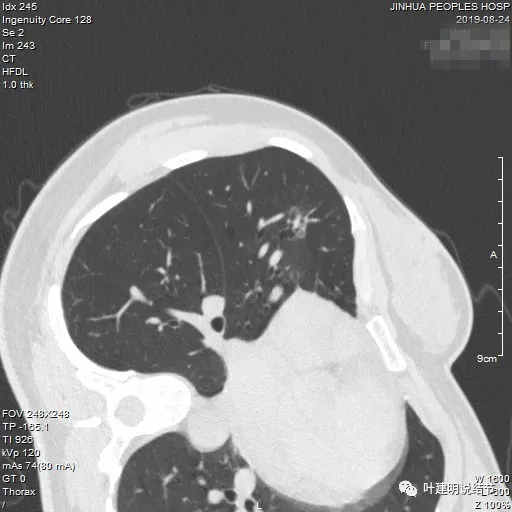

冠状位见病灶基本实性,小血管进入明显,囊壁厚薄不均,囊腔内壁不光滑,表面浅分叶。

矢状位显示较强的收缩力的样子,表面明显棘突的样子,而且囊壁密度杂乱,伴浅分叶征以及胸膜牵拉征。

前后最明显层面对比:

间隔才三个月,明显感觉更不舒服,更像恶性了些。